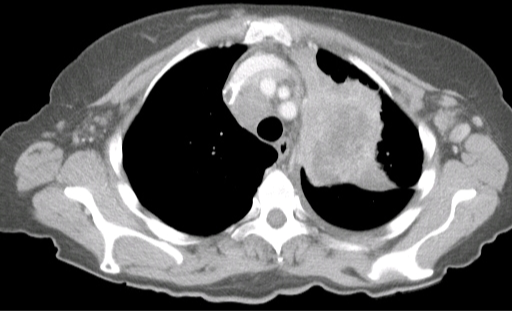

A 65-year-old woman comes to the office with several months of progressive cough and generalized weakness.  The patient has limited mobility and shortness of breath due to osteoarthritis and chronic obstructive pulmonary disease, respectively.  She also has difficulty standing from a chair, combing her hair, and putting dishes in overhead cabinets.  The patient's medical history includes hypertension and hyperlipidemia.  She quit smoking cigarettes 2 years ago but previously smoked 3 packs daily since age 20.  Blood pressure is 112/70 mm Hg, and pulse is 92/min.  BMI is 17 kg/m2.  Physical examination shows moderate weakness in the proximal muscles of her upper and lower limbs and loss of deep tendon reflexes.  CT scan of the chest is shown below. A 65-year-old woman comes to the office with several months of progressive cough and generalized weakness.  The patient has limited mobility and shortness of breath due to osteoarthritis and chronic obstructive pulmonary disease, respectively.  She also has difficulty standing from a chair, combing her hair, and putting dishes in overhead cabinets.  The patient's medical history includes hypertension and hyperlipidemia.  She quit smoking cigarettes 2 years ago but previously smoked 3 packs daily since age 20.  Blood pressure is 112/70 mm Hg, and pulse is 92/min.  BMI is 17 kg/m<sup>2</sup>.  Physical examination shows moderate weakness in the proximal muscles of her upper and lower limbs and loss of deep tendon reflexes.  CT scan of the chest is shown below.   Which of the following is the most likely cause of this patient's weakness? A) Acute inflammatory demyelinating polyneuropathy B) Autoantibodies against post-synaptic receptors C) Autoantibodies to voltage-gated calcium channels D) Immune-mediated muscle inflammation E) Multicentric central nervous system inflammation and demyelination F) Upper and lower motor neuron degeneration Which of the following is the most likely cause of this patient's weakness?